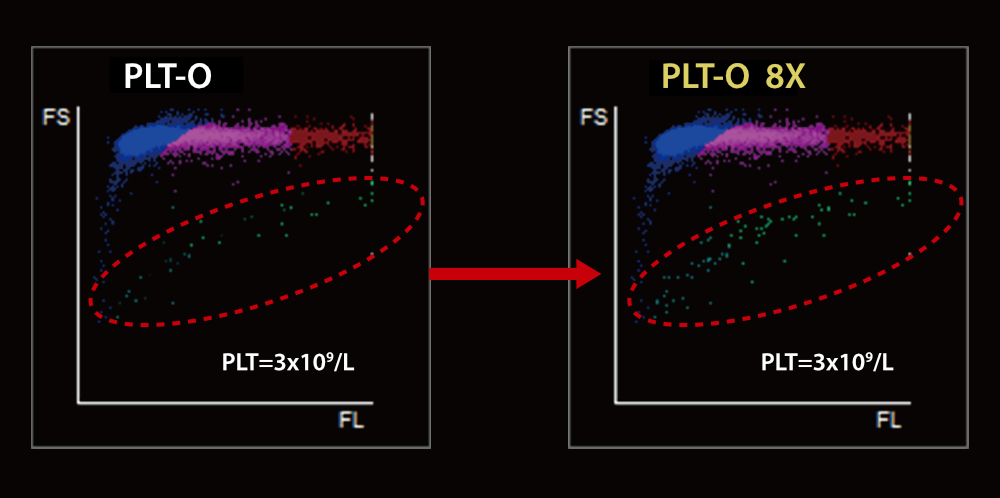

PLT-O with Multiple Counting for Low-count Platelet

There is no need to re-aspirate samples. The instrument will automatically conduct 8 times statistical analysis on low PLT count samples to improve the detection accuracy.

Scattergram before and after Auto 8x PLT-O counting